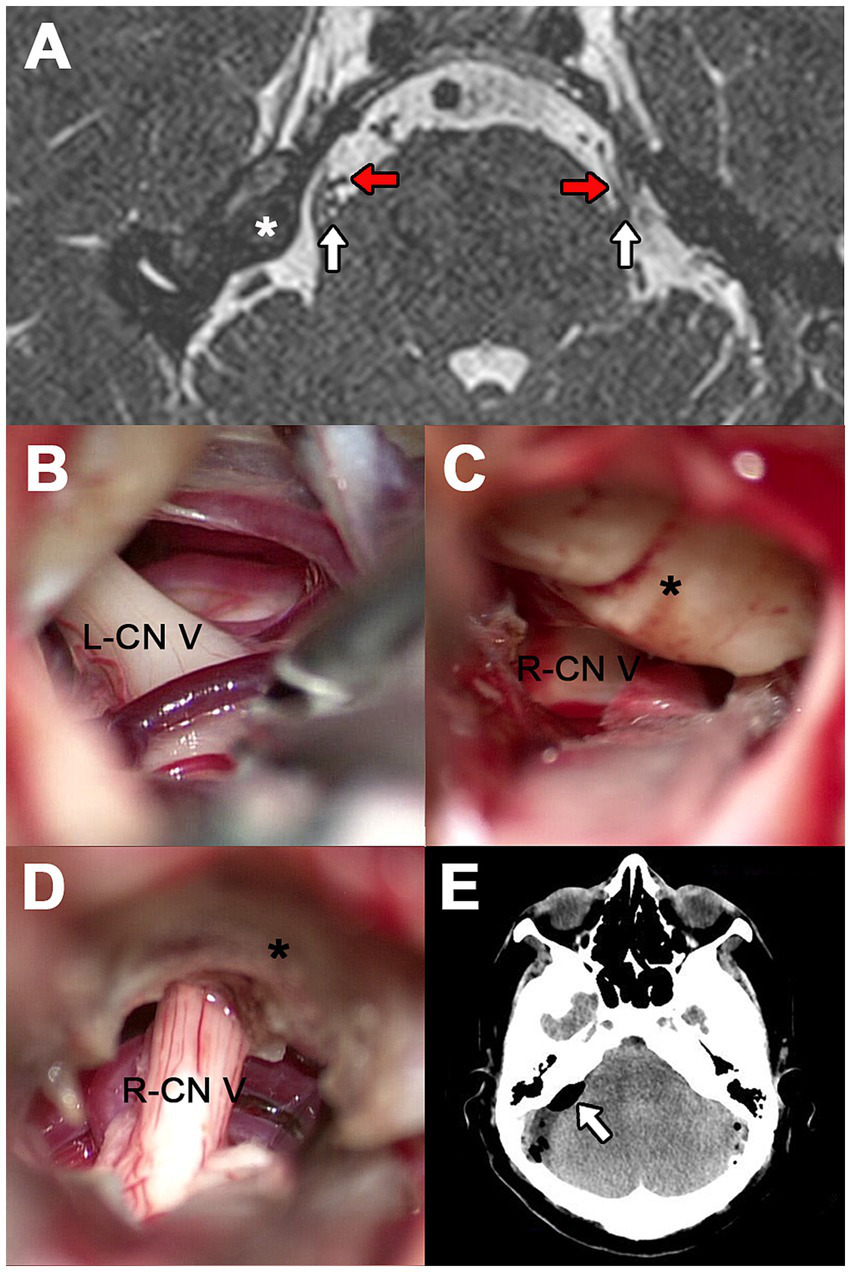

Figure 1

Case 1. (A) Axial 3D-FIESTA MRI at the level of the pons. The white arrows indicate the cisternal portion of CN V and the red arrows the contact vessels. (B) Surgical exploration on the right side showing SCA as the culprit vessel. (C) Suprameatal tubercle (asterisk) obstructing visualization of the left CN V. (D) Left-sided surgical exploration showing drilled suprameatal tubercle (asterisk) and redundant SCA as the offending vessel. (E,F) 3D reconstruction CT scan showing left and right retrosigmoid craniotomy, respectively.

Initially, a right MVD was performed. During the procedure, the superior cerebellar artery (SCA) and an unnamed vein were identified compressing the CN V (Figure 1B). The artery was gently separated from the nerve, and a Teflon pad was interposed. The vein was coagulated and resected. Immediately after closing the right approach, the patient was repositioned to expose the left side for a second, consecutive retrosigmoid approach. Upon opening the dura, a suprameatal tubercle approximately 3 mm in size obstructed the surgical view (Figure 1C). Drilling of this bony structure was necessary until a redundant SCA and another unnamed vein could be identified and separated using Teflon felts (Figure 1D). The suprameatal tubercle was not detected on the presurgical MRI (Figure 1A).

Postoperatively, a CT scan with 3D reconstruction was performed (Figures 1E,F). The patient reported hypoesthesia on the right side and paresthesia, otic fullness, and tinnitus on the left side. All these adverse events were transient. There were no major complications. Pain relief was immediate on both sides, with continued satisfactory results at 6 months of follow-up.